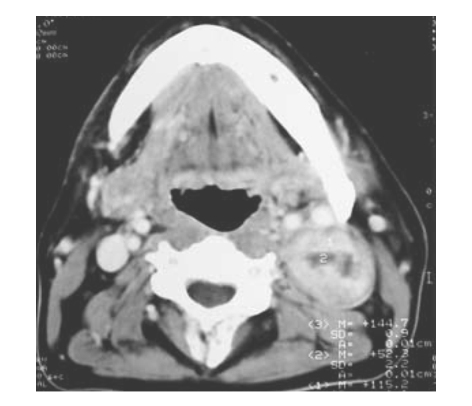

患者,女,43岁,发现左侧颌下包块2年多,近3个月明显增大。行CT增强扫描如图所示:

1.最可能的诊断是

2.若要明确肿瘤与邻近结构的关系,最好行以下哪种检查

正确答案:1.C;2.D